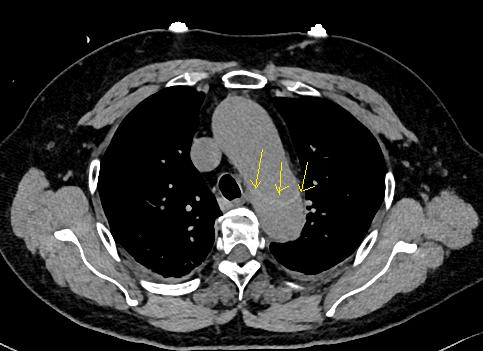

查到一篇文献,作者虽然用箭头标记了,并且是增强CT,但是鲁迅说:我大约肯定没有看出来,这是主动脉夹层!

图21